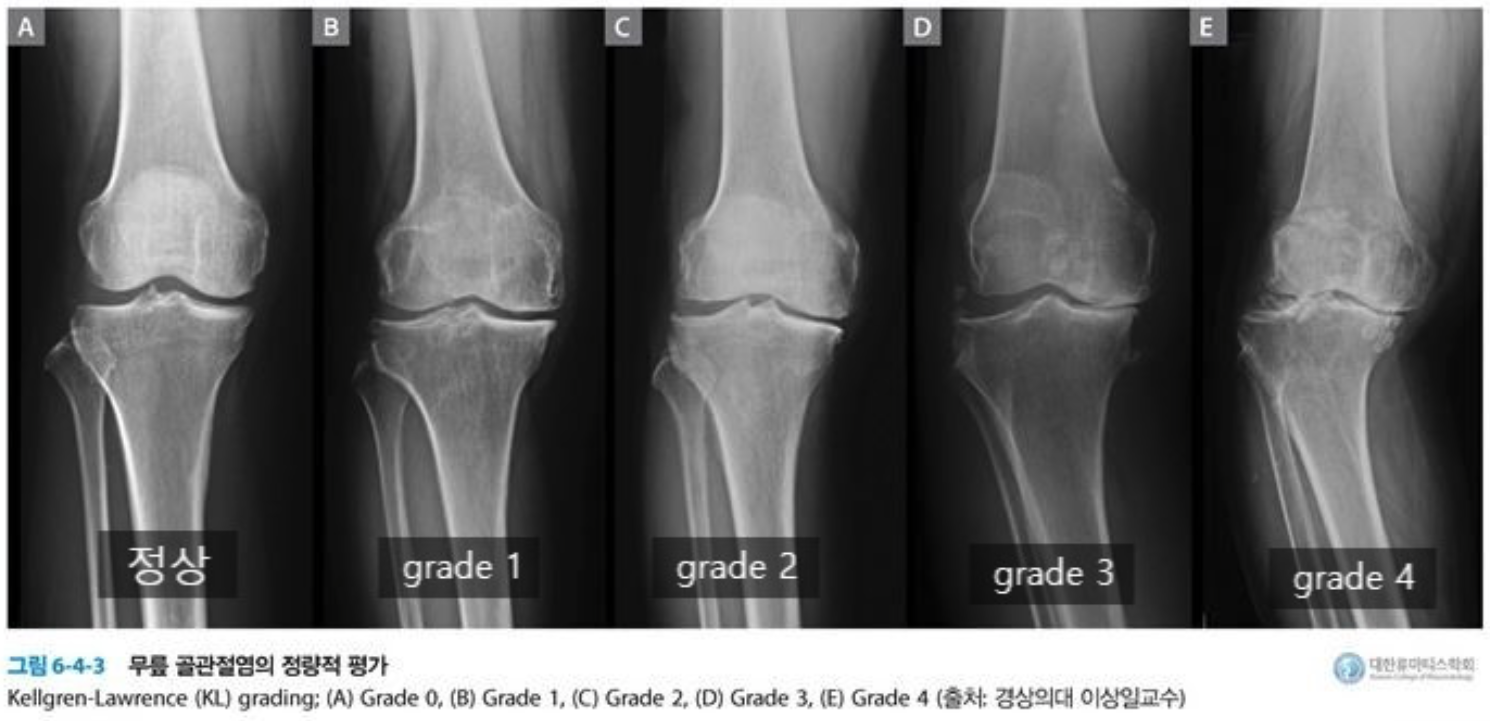

퇴행성 관절염은 진행단계에 따라 초기 - 중기 - 말기로 나눌 수 있으며 X-ray를 촬영하여 1기에서 4기까지 단계로

표현하기도 합니다.

| 단 계 | 단계별 설명 |

| 정상 | 방사선 사진(X-ray)상 별다른 이상이 없을 때 |

| 1 단계 | 경미한 관절공간의 협착이 관찰되고 골극이 형성되는 단계 |

| 2 단계 | 진행된 관절공간의 협착과 확실한 골극이 보이는 단계 |

| 3 단계 | 중증도의 관절공간의 협착 및 골극이 보이는 단계 연골하골의 경화 및 뼈의 변형이 발생 |

| 4 단계 | 관절공간의 현저한 협착 및 골극이 보이며 연골하골의 심한 경화와 뼈와 다리의 변형이 확인되는 단계 |